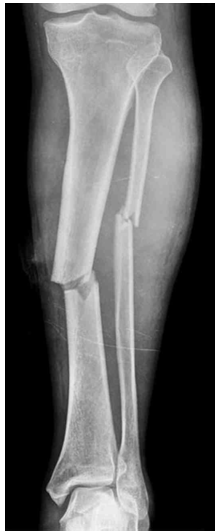

22세 남자가 1시간 전에 오토바이를 타고 가다가 택시에 부딪힌 후 응급실에 왔다. 왼쪽 다리가 아프다고 한다. 혈압 90/65 mmHg, 맥박 110회/분, 호흡 19회/분, 체온 37.1°C이다. 의식은 명료하다. 왼쪽 다리 X선사진이다. 왼쪽 다리를 부목으로 고정하였다. 4시간 후에 왼쪽 종아리 부위가 심하게 붓고 극심한 통증을 호소하여 진통제를 투여 하였으나 통증은 더 심해졌다. 왼쪽 발등동맥 맥박이 잘 만져지지 않는다. 혈액검사 결과는 다음과 같다. 치료는?

Lt. leg X-ray: Tibia/fibula shaft fracture

• Lt. leg X-ray에서 tibia/fibula shaft fracture가 확인된다.